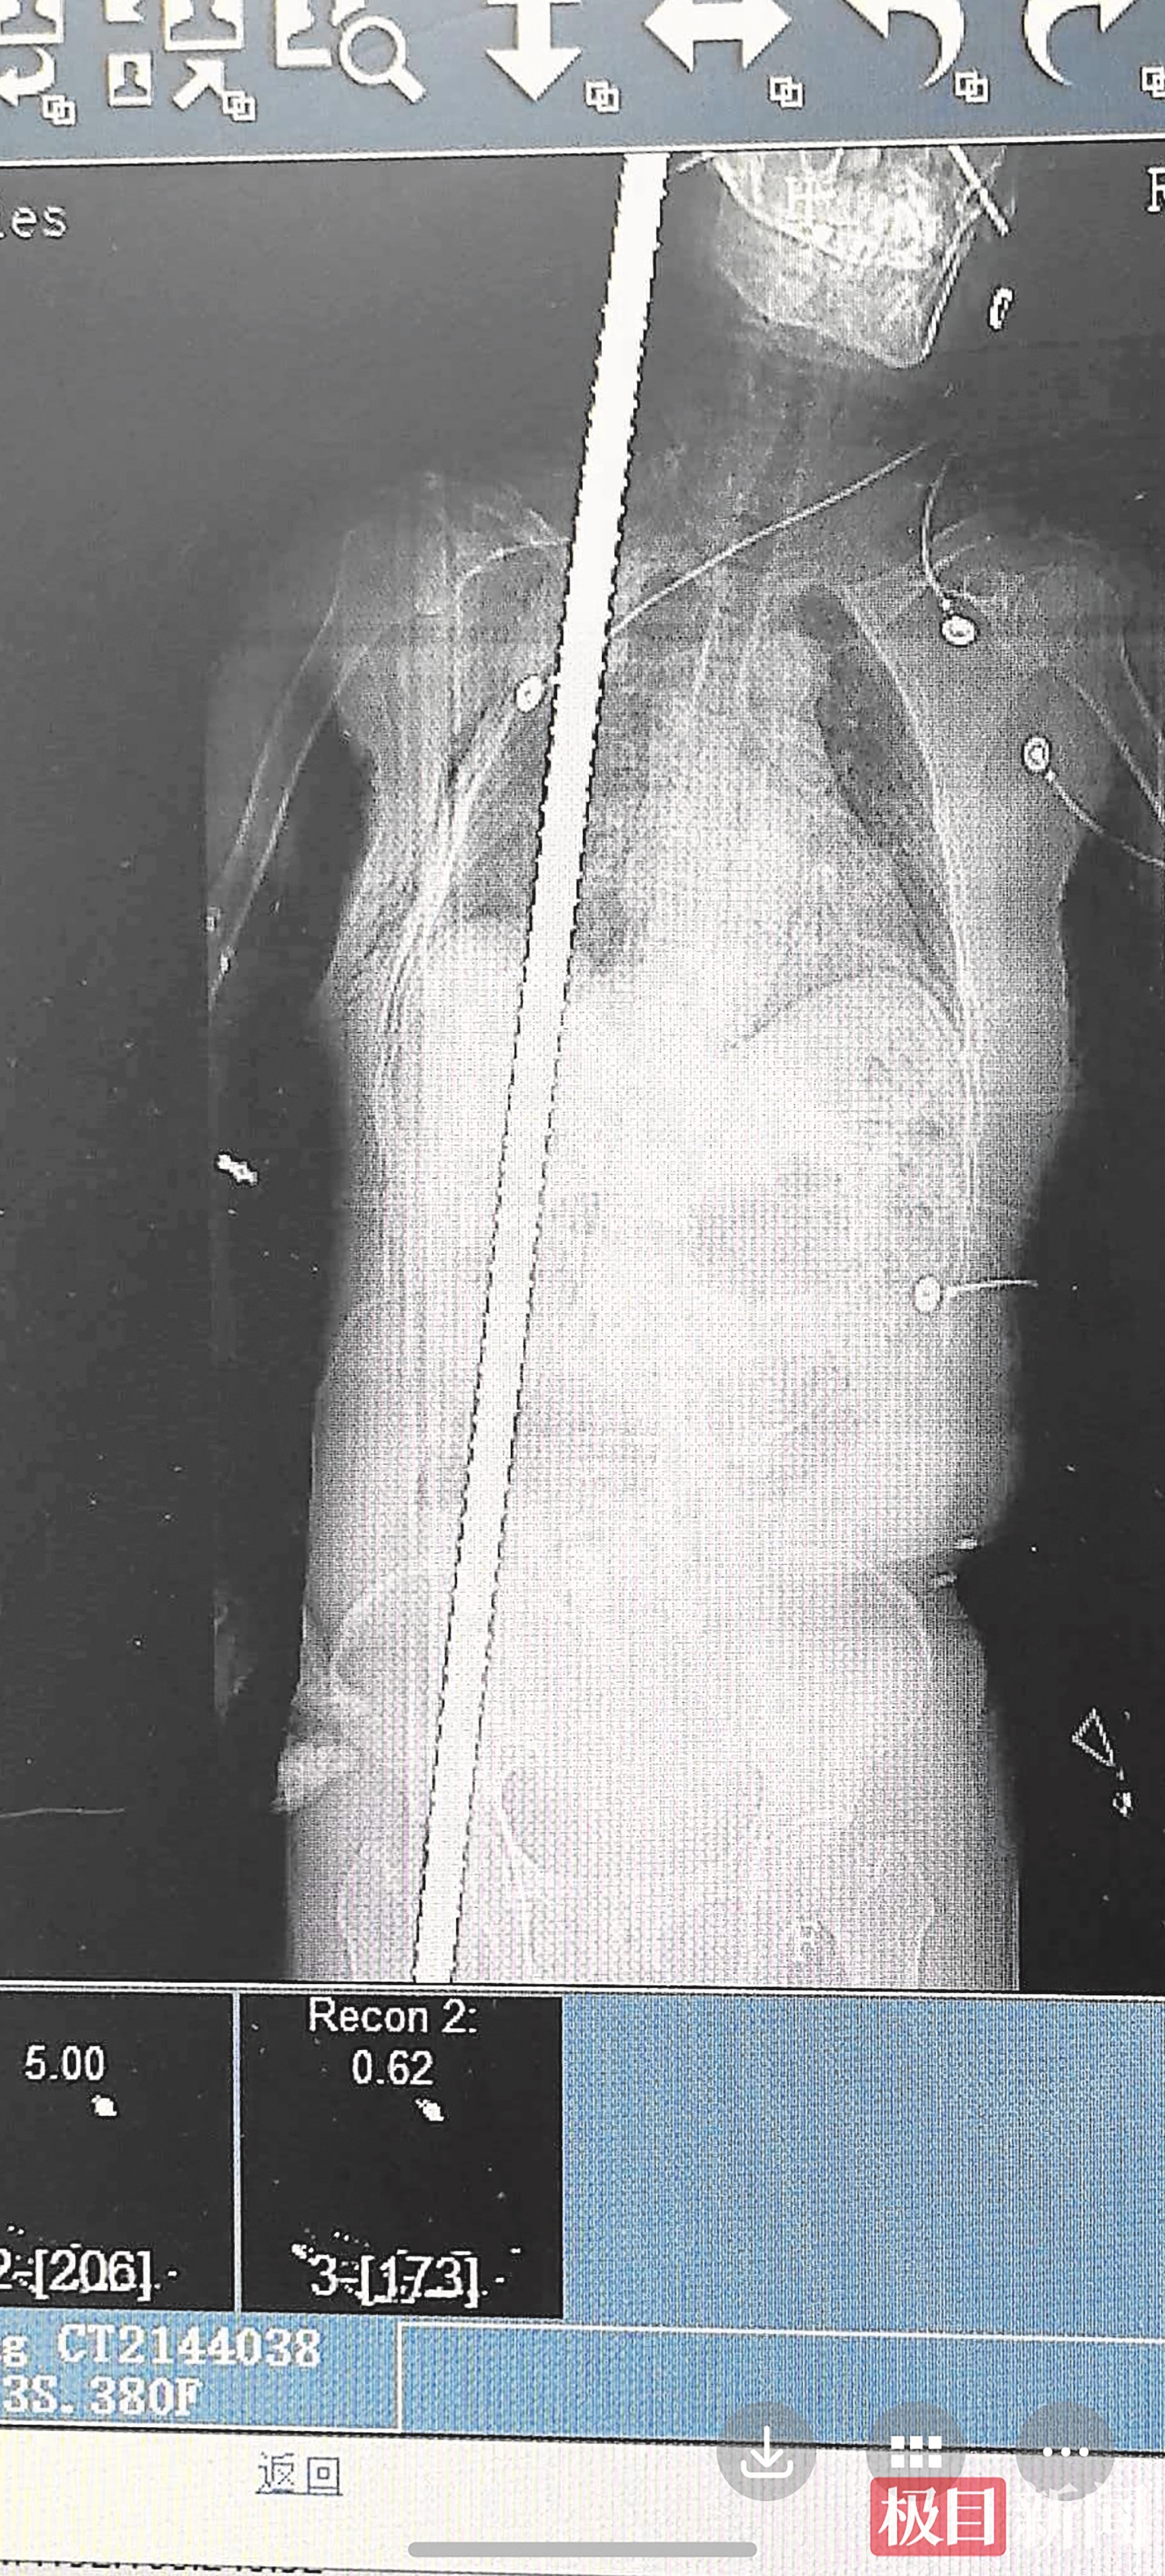

▲张女士在手术前进行了影像学检查

CT结果印证了最坏的担忧:钢筋在体内贯穿出一条极度凶险的“隧道”,它紧贴右侧锁骨下动静脉(人体上肢主要供血血管)、完全穿透右肺、刺破膈肌、紧邻肝门区(肝脏血流总枢纽)、损毁右肾、造成骨盆骨折,末端从大腿根部穿出。任何一处大血管破裂,或引发严重感染,都足以致命。